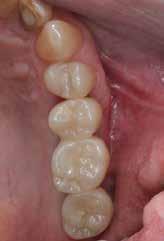

A fogpótlás készítésének lépései

Hathetes gyógyulás után a lágyszövetek kiválóan gyógyultak, és minden implantátum megfelelően osszeointegrálódott, amelyet a radiológiai vizsgálat is megerősítetett (9. és 10. ábra).

Nyitott kanalas lenyomatvételi fejeket csatlakoztattunk az implantátumokhoz, és elasztomer lenyomat-anyagot fecskendeztünk köréjük és a lenyomatkanálba, hogy egyfázisú lenyomatot vegyünk. A minta laboratóriumi elkészítését követően a kimart vázra kerámia leplezés került, amelyet megfelelő festéssel tettek még természetesebbé. Ezt követően a pótlást közvetlenül az implantátumokhoz csatlakoztattuk, majd ellenőriztük a kontaktpontot és az okklúziót. Minden csavart 35 Ncm-es nyomatékra húztunk, majd a csavarnyílásokat teflonszalaggal és fényre kötő kompozittal zártuk (11. ábra).

A végső röntgenfelvételen láthatjuk az osszeointegrálódott implantátumokat, valamint a stabil kresztális gerincet az azonnal behelyezett, a rövid és a ferde, a tuberben elhorgonyzott implantátum körül (12. ábra).

A páciens teljesen elégedett volt az esztétikai és a funkcionális eredménnyel is, továbbá lenyűgözte a kezelés rövidsége, valamint a minimálisan invazív megoldása.